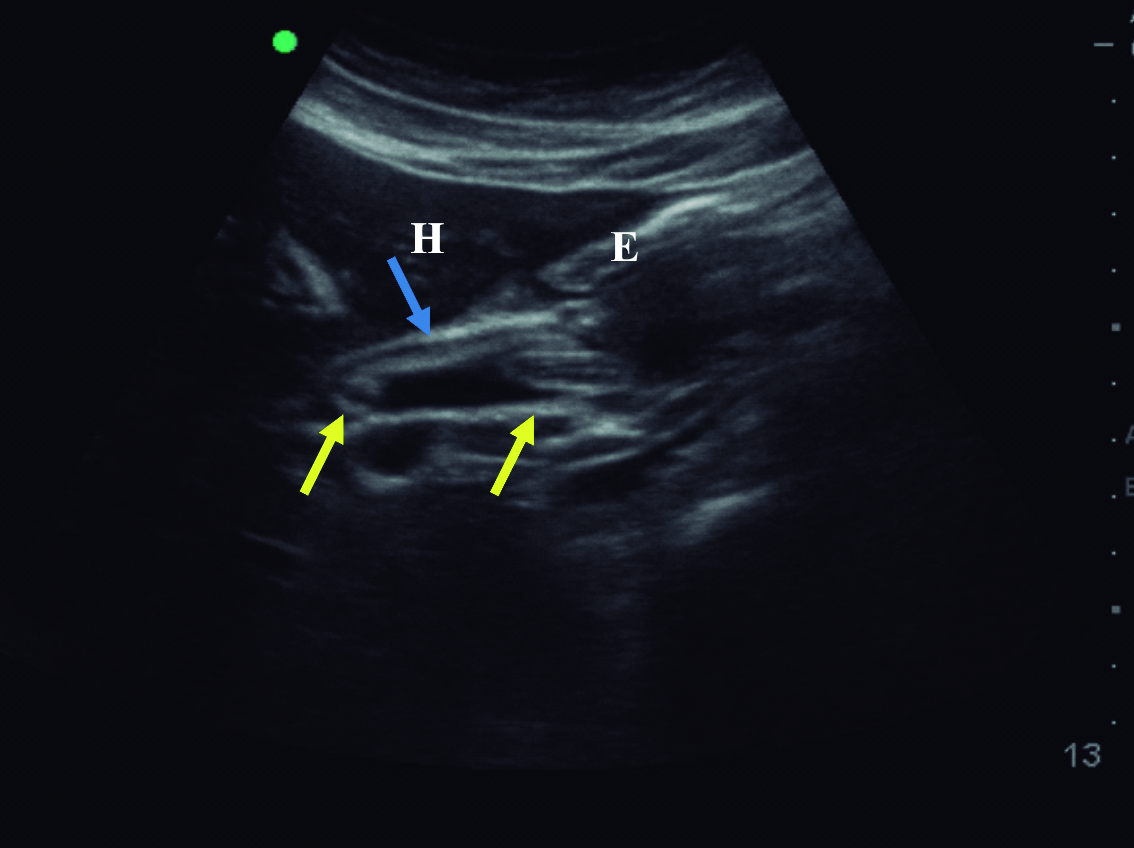

Figura 1. Ultrasonido en modo B

a) Corte transversal a nivel de epigastrio, en el cual se identifica colédoco dilatado (flecha azul), ocupado por el Ascaris plegado sobre sí mismo (flecha amarilla).

b) Corte longitudinal sobre el colédoco supraduodenal, en el cual se observa el Ascaris plegado sobre sí mismo (flechas amarillas) dentro del colédoco dilatado (flecha azul). H: Lóbulo hepático izquierdo, E: Corte transversal del antro gástrico, VP: Vena porta.